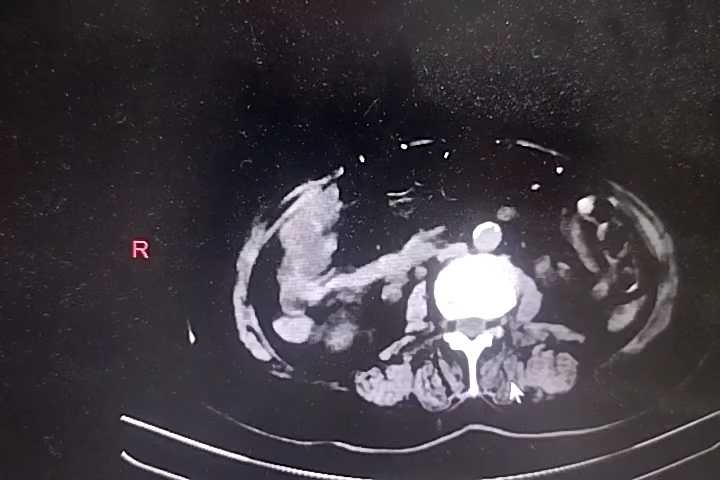

胸部+全腹部CT结果回报:双肺支气管炎,通气不良,双肺底多发索条,考虑1、膨胀不良2、慢性炎症,左肺下叶钙化灶,主动脉钙化,食管裂孔疝,纵隔多发淋巴结,肝门区钙化灶,胆囊密度低密度增高,考虑胆汁淤积,右肾囊肿?建议强化,双肾盂、输尿管扩张,膀胱过度充盈,考虑尿潴留,结合临床,直肠积粪密切观察病情变化。